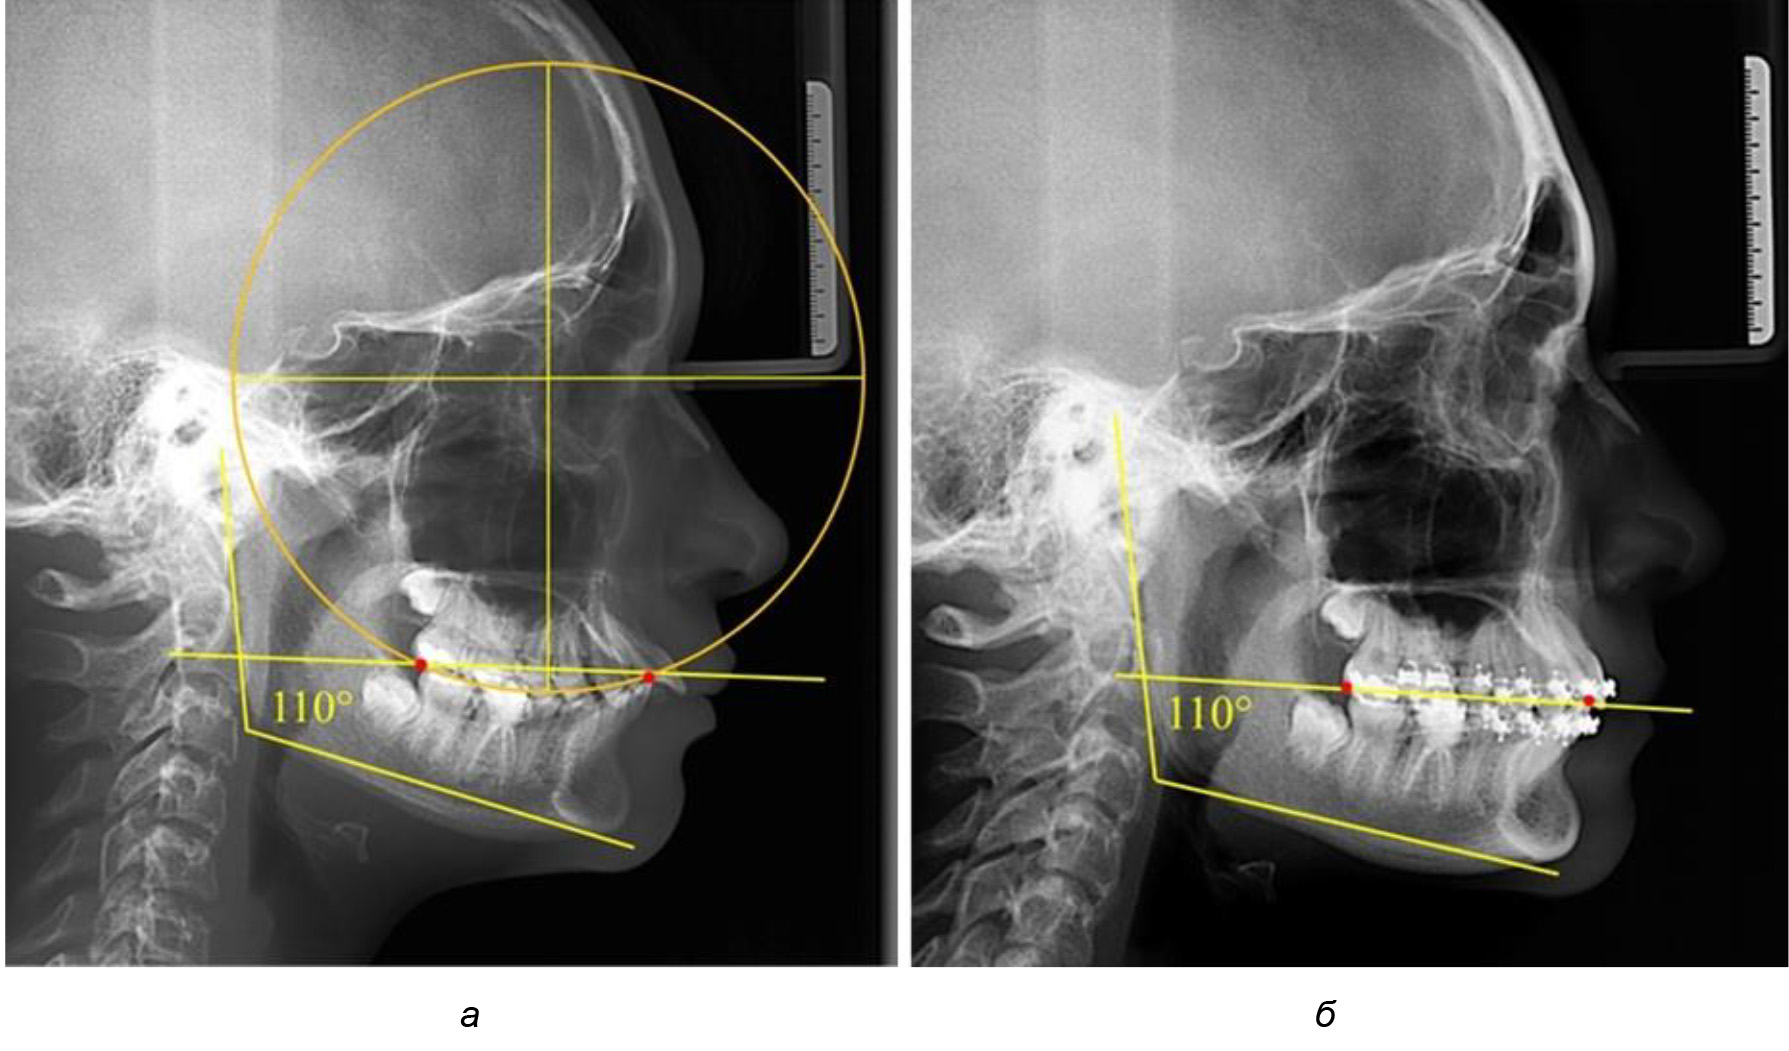

Таким образом, проведенное лечение техникой «прямой» дуги способствует нормализации окклюзионного равновесия и торку передних зубов, однако не соответствует оптимальному окклюзионному статусу, характеризующему физиологическую окклюзию. При этом величина нижнечелюстного угла оставалась на прежнем уровне (рис. 5).

Рис. 5. Особенности ТРГ при патологической кривой Spee до лечения (а) и после лечения (б) техникой «прямой» дуги

После лечения пациентов техникой «прямой» дуги, так же как и в 1-й подгруппе, было отмечено увеличение сагиттального размера окклюзионной лини в среднем на (2,38 ± 0,83) мм. Окклюзионная линия практически касалась окклюзионного контура всех жевательных зубов, и отмечалось практически полное отсутствие кривой Spee, так же как и у людей 1-й подгруппы 2-й группы (рис. 6).

Рис. 6. Особенности ТРГ при оптимальной кривой Spee до лечения (а) и после лечения (б) техникой «прямой» дуги

Таким образом, проведенное лечение техникой «прямой» дуги способствует нормализации окклюзионного равновесия и торку передних зубов, однако не соответствует оптимальному окклюзионному статусу, характеризующему физиологическую окклюзию. При этом величина нижнечелюстного угла оставалась на прежнем уровне.